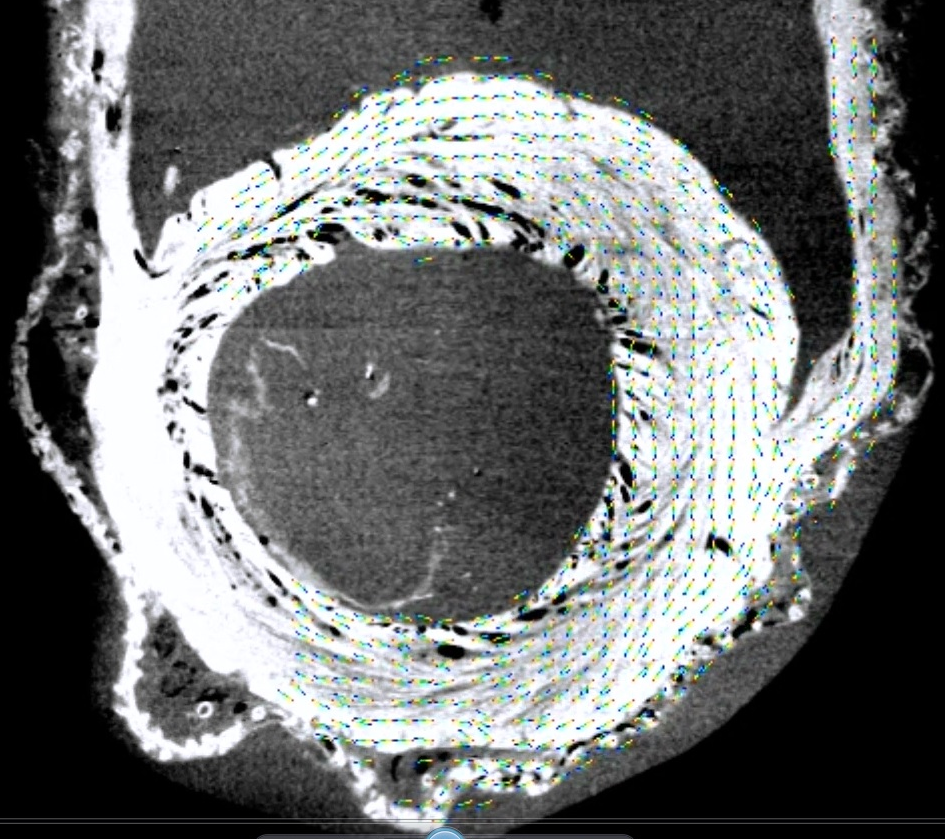

重症心不全における心筋配向変化が心機能増悪をもたらす機序の解明

(科学研究費基盤B)

重症心不全における心筋配向の変化と乱れが心収縮能と拡張能・心臓リモデリングに及ぼす影響をMicro CTと心機能シミュレーション技術を用いて解析し、心不全悪化のメカニズムを力学的観点から明らかにすること

【研究背景】

心不全が進行した心臓では、心形状が円錐形から球状化し、心筋配向がらせん構造から水平方向に傾き、さらに収縮効率が悪化する(図1)。さらに心筋シート(右図)の傾きは心室壁伸展に伴い、垂直方向に傾く。

【研究内容】

MicroCTを用いて正常心と不全心の心筋配向変化、心筋シートの傾きを評価する(名古屋大学工学部森健策教授研究室)。UT-Heart研究所の心臓シミュレーション技術に上記結果を組み込み、心機能(収縮能&拡張能)に与える影響を検討する。